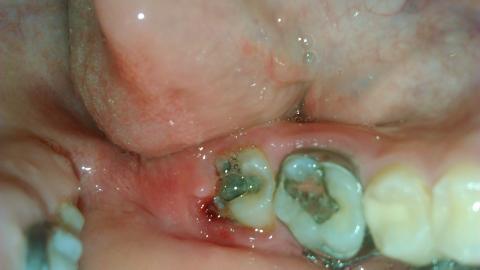

Pro větší náhled klikněte na obrázek

Dobry den,prosím vas o radu. Vcera som cítila taky zvlastny pocit okolo osmicky, no rano som sa zobudila na to,ze ma to boli a mam to opuchnuté,červené. Mam 16 rokov,na zuboch nosim uz par rokov strojcek, kedze som ich mala dost krive.vzhladom na to,neviem,ci mam dostatočnu dentalnu hygienu.vlozila som aj foto a za akukolvek odpoved budem vdacna,pokym nebude možné navštíviť svojho zubara.myslite,ze je to zapal?

Dobrý den, tohle nevypadá na zánět, ale jde o prořezávání osmičky. Bohužel se toto stává, osmičky rostou dlouho a tyto problémy se mohou vyskytovat. Můžete zkusit lokální dezinfekční prostředky typu Tamtum verše, nebo navštívit zubaře, který dáseň mírně nařízne a uvolní tak tlak rostoucího zubu na ni.